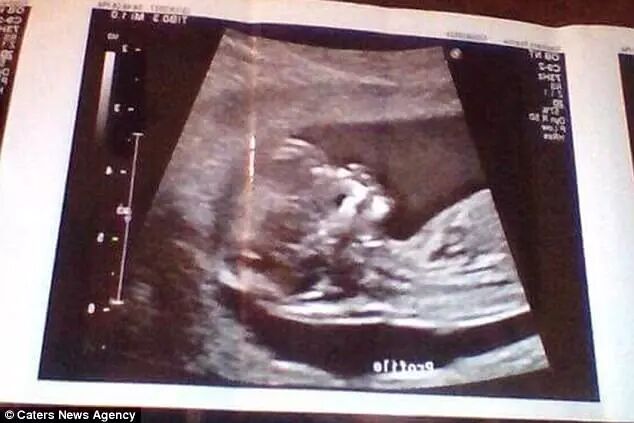

但,人家真的就是怀孕6个月了,有产检照片为证:

照片中的女孩叫Reanna Stephens,才18岁,来自美国。